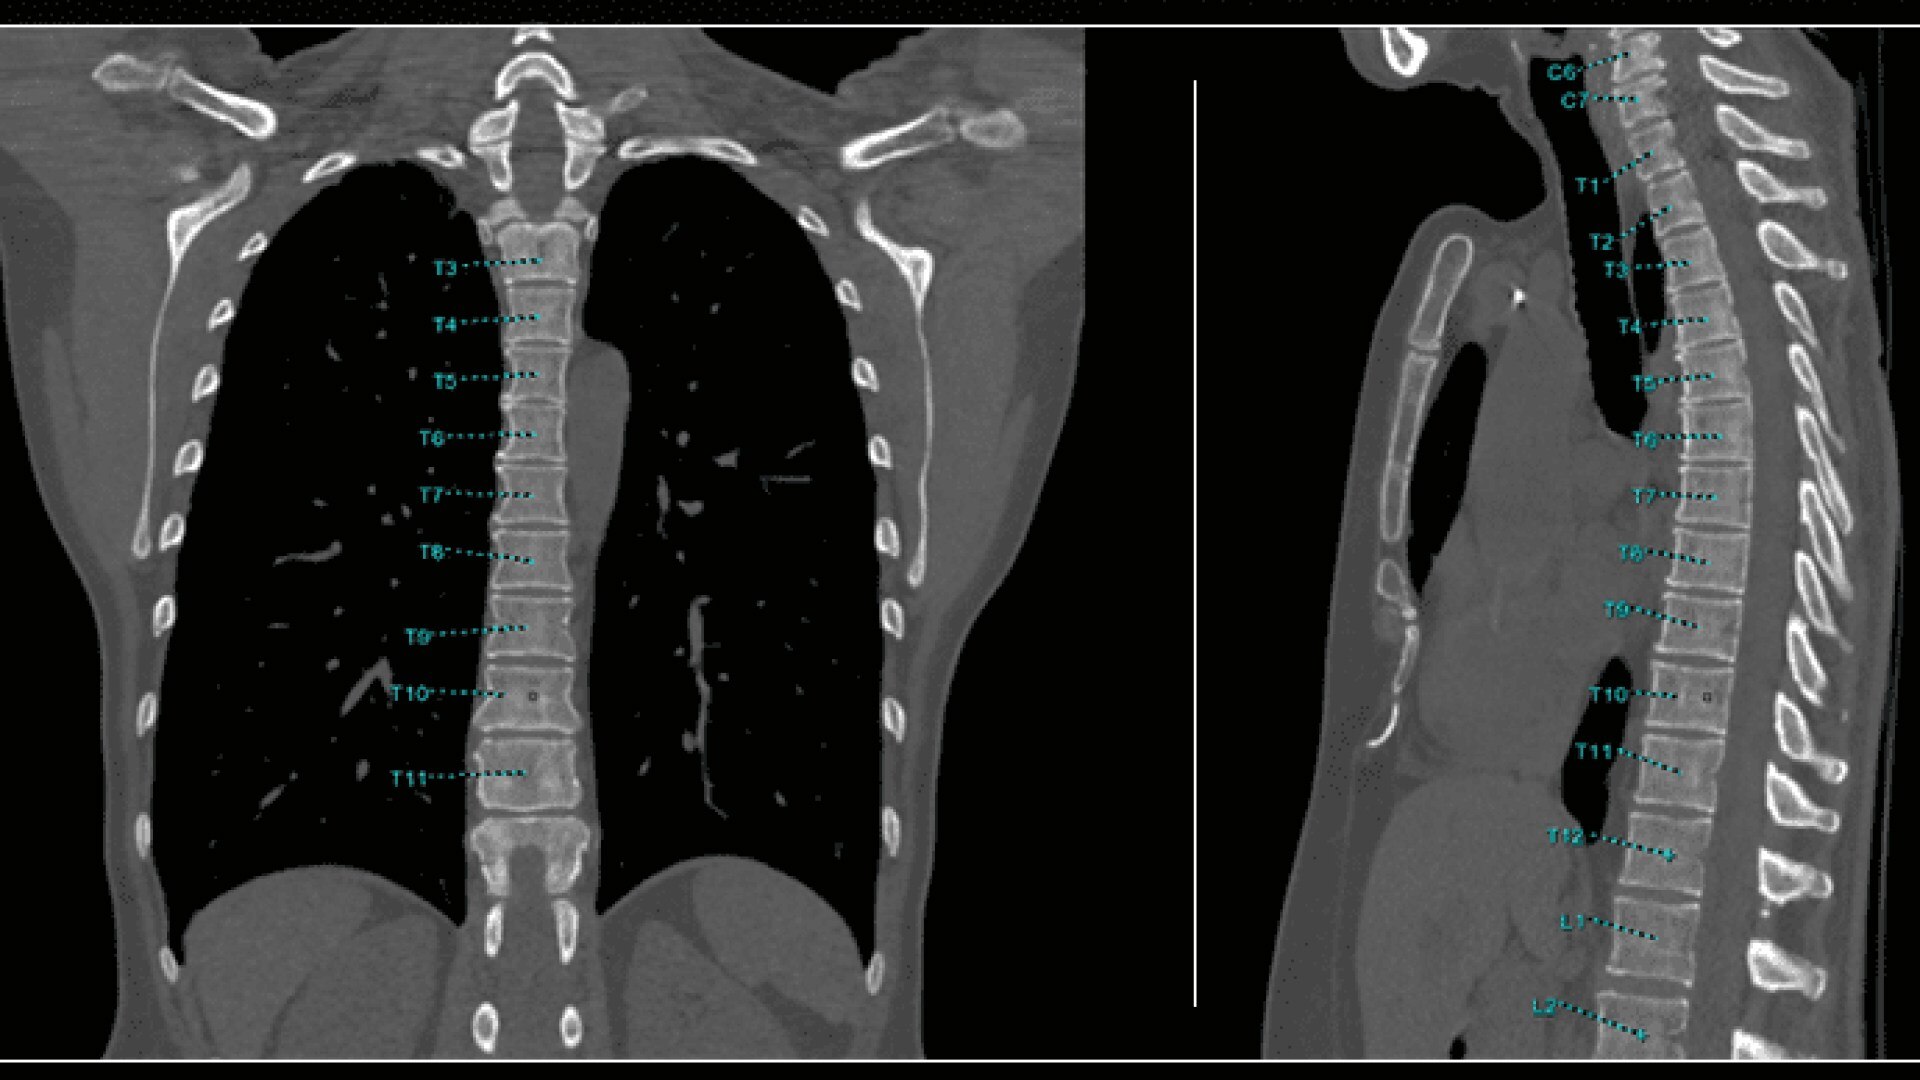

Bone VCAR

Spine assessment with deep-learning based CT application.

Automated curved reformats to aid in rapid reading and reporting.

• Automated generation of a 3D trace to generate oblique and straightened reformat views

• Automated generation of oblique views perpendicular to vertebral bodies and disc spaces

• Works on full spine acquisitions as well as limited acquisitions containing segments of the spine